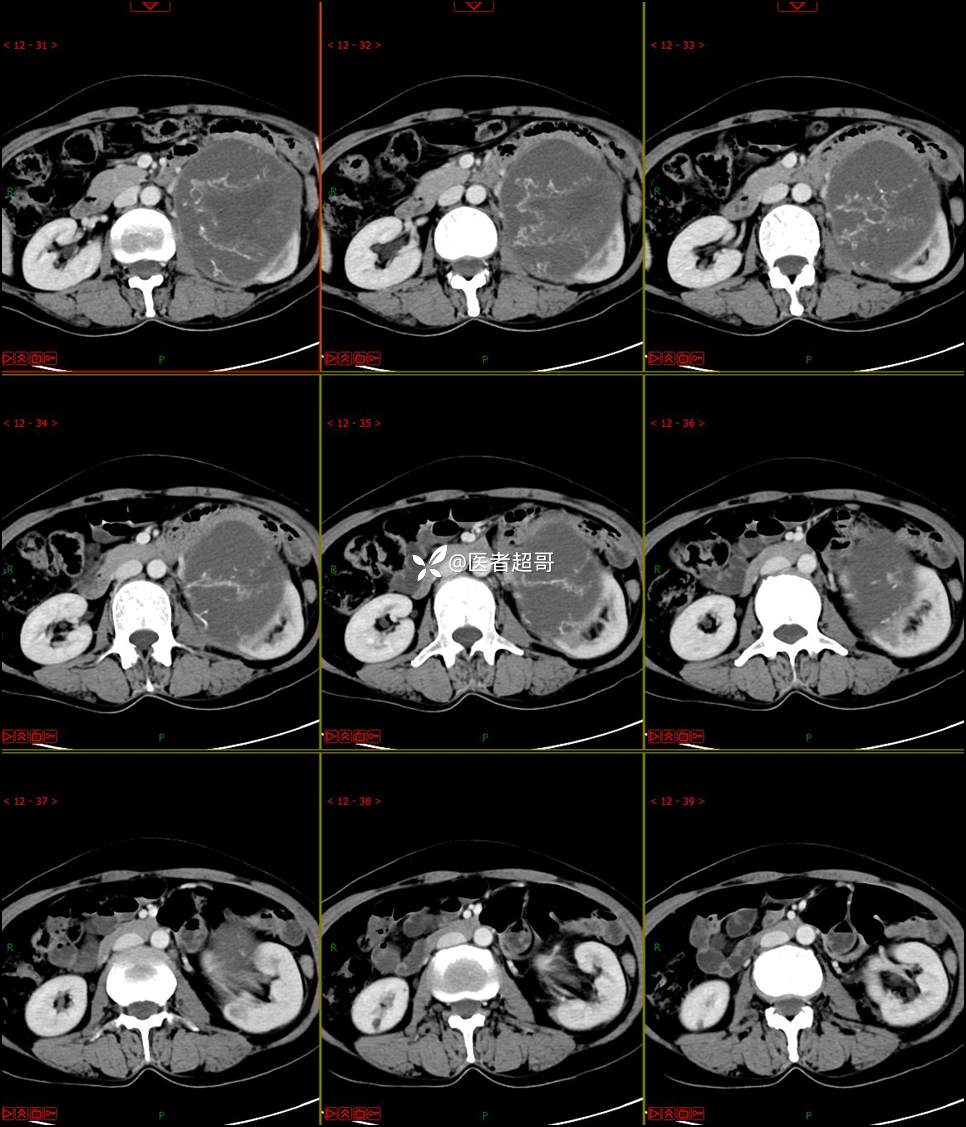

【影诊笔记768】肾脏肿瘤?肾上腺肿瘤?请诊断分析!

女 57岁 0200908 01

主 诉:发现左肾肿物7月余

现病史:患者7月前因左侧腹部疼痛不适,就诊市人民医院,行CT平扫:左侧肾上腺区混杂密度肿块,考虑肿瘤合并出血,行保守治疗后症状缓解出院,左侧下腹部及左侧髋部疼痛不适,无尿频、尿急、尿痛,无肉眼血尿,无寒战、发热,今患者为求进一步诊治,就诊我院,门诊以“左肾肿物”为诊断收入院,患者自发病以来,神志清,精神可,饮食睡眠可,小便如上述,大便正常,体重未见明显改变。